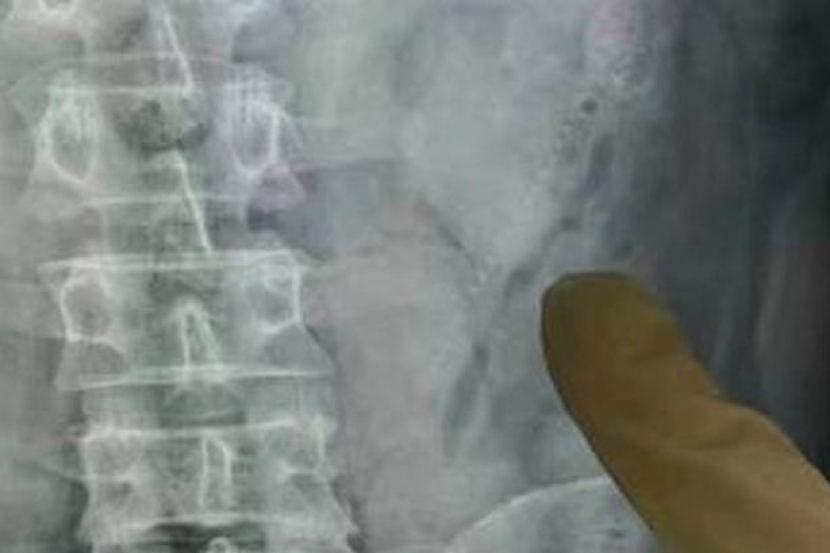

Doktor mendapati lelaki berkenaan berisiko dijangkiti kuman di bahagian usus dan terpaksa menjalankan pembedahan untuk mengeluarkan ikan tersebut yang pertama berukuran kira-kira 15 sentimeter.

Namun mereka pada awalnya gagal mengesan ikan kedua dalam usus tersebut sebelum menyedari kesan luka pada organ tersebut.

"Ikan kedua berukuran 1.2 sentimeter tersangkut pada bahagian kanan perut pesakit tersebut.